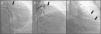

A 64-year-old Caucasian male with a history of coronary artery bypass grafting (CABG) [internal mammary artery (IMA) graft to the left anterior descending artery (LAD) and saphenous vein graft to right posterior descending artery (PDA)], presented with stable angina with a positive treadmill exercise test. Coronary angiography (CAG) documented occlusion of both middle LAD and IMA grafts (Figure 1, panel A); no significant lesions were found in the circumflex artery or the saphenous vein graft. The CAG performed prior to surgery is shown in Figure 2.

After a myocardial perfusion scintigraphy confirming viability in LAD territory, an angioplasty was performed. A new large vessel was visible after mid-LAD dilatation (Figure 1, panel B, supplementary film 1). The images were suggestive of a fistula or a shunt. A 4.0×18-mm drug-eluting stent was successfully implanted. The patient remained stable throughout the procedure.

CT angiography showed a fistula from the middle segment of the LAD to the coronary sinus (Figure 1, panel C). Excluding the fistula by implanting a covered stent was then considered. However, when performing the initial CAG, complete stent restenosis had occurred, resulting in both LAD and fistula occlusion (Figure 3). A silent infarction had probably occurred. A new ischemia test was performed, documenting necrosis without viability. A conservative approach was therefore chosen.